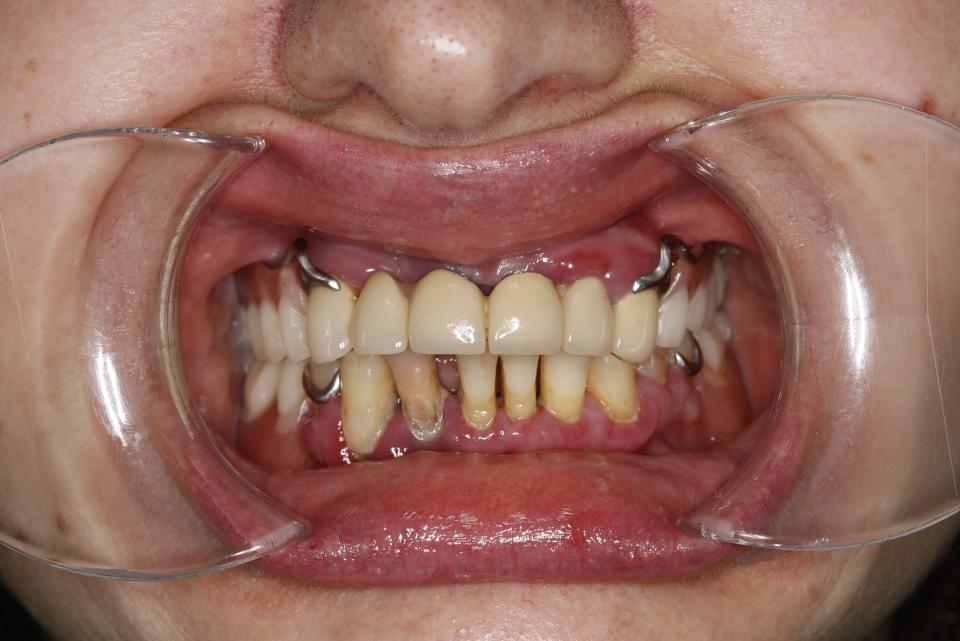

paraschyk1 Опубліковано: 6 червня 2018 Автор Опубліковано: 6 червня 2018 Вот фото зубов где коронки были сделаны пять лет назад с прайсом вдвое дороже чем у меня сейчас. Зубы после такого- трупы.А все от ненадлежащего качества работы и пох.зма в отношении в людям.

paraschyk1 Опубліковано: 6 червня 2018 Автор Опубліковано: 6 червня 2018 Вот фото где также коронки простояли четыре года и пац только выплатил кредит по ним,а спустя два мес. пришлось все убрать и переделывать,ессно за новые тугрики.